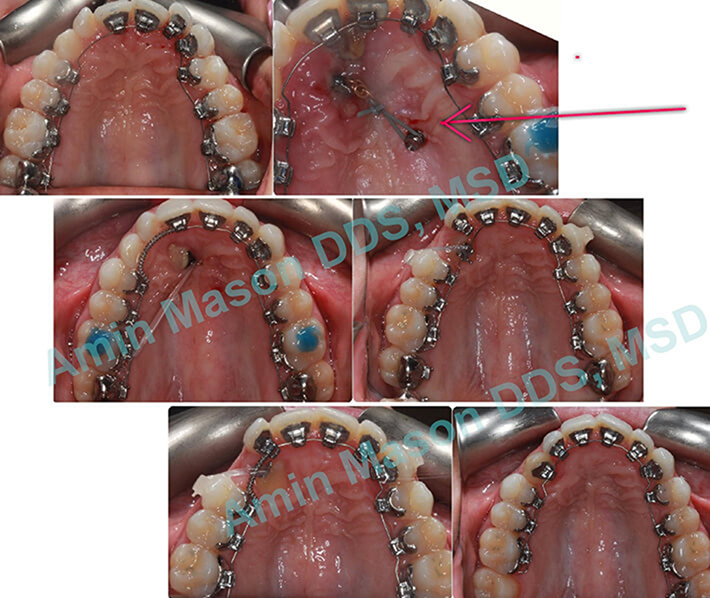

TADs Used To Guide Impacted Canines

Adult patient impacted tooth in the palate. TAD in palate was used to guide the canine into the arch.